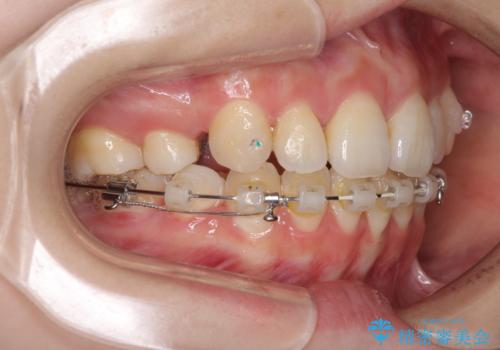

- 矯正装置

- ハーフリンガル

裏側矯正特有の抜歯スペースに前後の歯が倒れ込む状態が長く続き、改善に長期間を要しました。